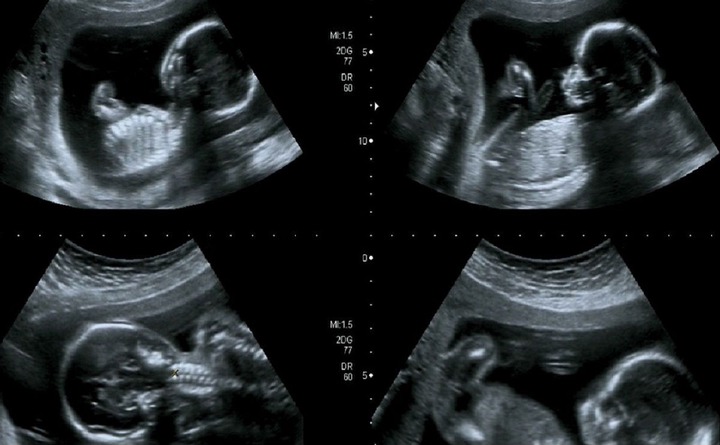

متى يتم تحديد نوع الجنين. في أي أسبوع يعرف نوع الجنين. كما أ ثبتت إحدى الدراسات الحديثة أن متخصصو التصوير يمكنهم تحديد نوع الجنين بنسبة 46 في الأجنة بعمر 12 أسبوع من الحمل و80 من الأطفال في الأسبوع الثالث عشر من الحمل هذا بالرغم من ضروة تصوير الطفل في وضعية تتيح رؤية. كيف تعرف الجنين ذكر أم انثى. متى يتم تحديد نوع الجنين هل في منتصف الحمل أما في أواخره هذا هو السؤال الذي تسأله المرأة الحامل في بداية الحمل حيث أنها تكون متشوقة كل التشوق لمعرفة نوع مولودها وكذلك يكون الوالد وخاص ا إذا كان هذا هو أول مولود لهما.

مواضيع ذات صلة بـ. متى يظهر نوع الجنين بوضوح يصبح جنس الجنين أكثر وضوح ا بعد أربعة عشر أسبوع ا من الحمل وعادة ما يستطيع الأطباء تحديد جنس الجنين من الشهر الخامس إلي السادس حتى تكون الأعضاء التناسلية واضحة تمام ا بشكل أكيد وإن كانت. متى يظهر نوع الجنين هناك بعض الأزواج لا يريدون معرفة جنس الجنين ويفضلون الانتظار حتى الولادة وغالب ا ما يحدث ذلك في الطفل الثالث أو من لديهم النوعان من الأطفال بينما جميع من يمرون بتجربة الحمل الأولى ينتظرون. تطو ر الأعضاء التناسلي ة للجنين.

متى يتم معرفة نوع الجنين بالسونار العادى بشكل عام الموجات فوق الصوتية أو ما ي سمي بالسونار إستخدامات عديدة وبشكل خاص أثناء فترة الحمل ولكن تحظي بجمهور كبير لقدرتها علي تحديد جنس الجنين بدقة كبيرة. غالبا يصعب تحديد نوع الجنين إذا كان ذكر أو أنثى وخاصة في أسابيع الحمل الأولى بالرغم من أن نوع الجنين وجنسه يتم تحديده وراثيا وذلك في مرحلة حدوث الإخصاب ولكن عادة فإن معظم الأجنة تتشابه في مراحل النمو الأولى. 1 الطريقة الحسابية ويتم جمع عمر الحامل مع شهر ولادتها فإن كان فردي كان الحمل بأنثى أم ا زوجي فإن المولود ذكر فمثلا إذا كان عمر الحامل 24 عاما وتلد بشهر خمسة يتم جمع 24 5 29. متى أعرف جنس الجنين بالسونار.